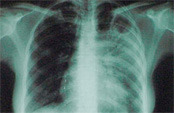

За год от туберкулеза умерли почти два миллиона человек

Об этом сообщили во Всемирной организации здравоохранения. По данным доклада ВОЗ, большая часть случаев заболевания была зафиксирована в странах Юго-Восточной Азии и Африки, передает РИА Новости.

Эксперты организации отмечают, что ежедневно туберкулез уносит жизни почти пяти тысяч человек. В России, как сообщает ВОЗ, за год выявлено 117 тысяч случаев этого заболевания.